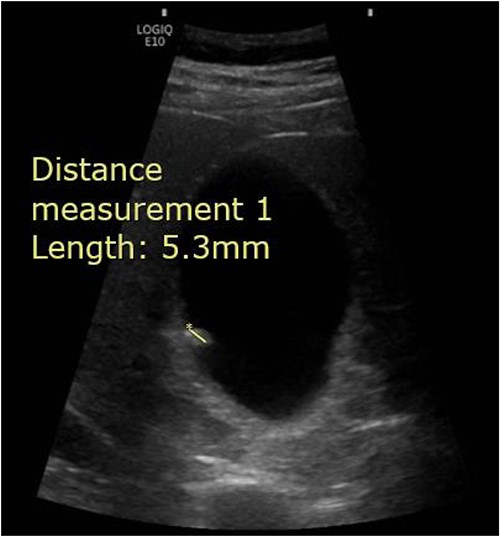

A 65-year-old male presented to the Surgical Assessment Unit with a 6-day history of right upper quadrant and epigastric pain. He underwent an ultrasound scan that showed a 5 mm mobile gallstone in a thin-walled non-tender gallbladder and fatty infiltration of the liver (Fig. 1). The biliary ducts were of normal calibre. The patient was given a course of antibiotics and discharged home with a plan to follow-up in the Ambulatory Surgical Clinic in a few weeks’ time. Unfortunately, his pain persisted and had migrated to the right iliac fossa. Apart from the pain, he was otherwise well. He was discharged home with an extended course of antibiotics and a plan to return for a laparoscopic cholecystectomy on the rapid access theatre list.

Abdominal ultrasound demonstrating the presence of a 5.3 mm stone within the gallbladder.